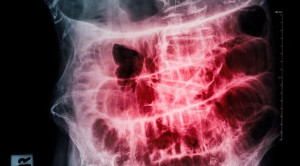

• Pemeriksaan Appendicogram untuk Diagnosis Appendisitis

Pemeriksaan Appendicogram untuk Diagnosis Appendisitis

Saat ini, penggunaan appendicogram dalam diagnosis appendicitis mulai ditinggalkan karena semakin digantikan dengan modalitas pencitraan lain, seperti USG dan CT scan.[1] Appendicogram...(Baca Selengkapnya)